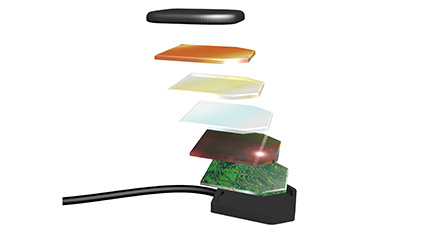

超薄CMOS传感器,可以确保患者体验舒适度。在患者口腔中放置定位传感器具有一定挑战性。多年来口腔数字传感器技术得到进一步提升,已实现患者体验舒适度。Vatech集团研发中心测试了口内传感器的厚度,并在使用CMOS芯片的同时引入新技术,以最大限度减少拍片疼痛感。

圆角设计将舒适度最大限度地放置在软组织上。 患者感到疼痛是因为脆弱的口腔粘膜受到来自硬传感器角落的压力。圆角可以减轻疼痛,但它有会减少活动图像区域,进而维持它们之间完美的平衡技术。 符合人体工程学的3种不同尺寸设计,可满足各种情况的需求。圆形和切割的边缘为患者提供了尽可能好的舒适度。更重要的是,vatech独特的超薄CMOS口内传感器几乎适合所有患者。 数字传感器的优点是:提供快速高效的工作流程。链接USB接口,可实现即时图像传输和高度便携的图像捕捉。 EzSensor Classic防护等级为IP68,是最高级别的入口防护[IP],同时还可防尘。